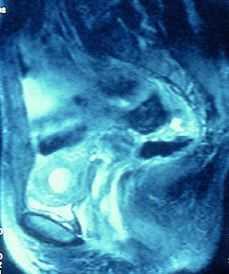

El estudio ecotomográfico del abdomen pélvico (mediante ecografía abdominal con repleción vesical, al tratarse de una joven sin relaciones sexuales previas), muestra un útero en anteversión con un diámetro longitudinal de 7,5 cm y un diámetro anteroposterior fúndico de 3,5 cm. Los cortes transversales muestran dos áreas correspondientes a endometrio divididas por un septo que llega a cérvix. En la cavidad izquierda se visualiza un moderado hematometra, lo que sugiere que se trata de una cavidad no comunicante (Fig. 2). Ambos ovarios presentan unas características tanto morfológicas como ecográficas normales. En la Resonancia Nuclear Magnética (RNM) se observa la presencia de dos hemicavidades uterinas separadas por un septo total. El hemiútero derecho presenta una morfología y cavidad conservadas, con un cérvix también de características normales. Sin embargo, el hemiútero izquierdo presenta una distensión de su cavidad, de señal hiperintensa tanto en las secuencias potenciadas en T1 como en las potenciadas en T2, compatible con hematometra. No se observa comunicación de la misma con el cérvix. Ambos ovarios presentan múltiples folículos con un tamaño y morfología dentro de los límites de la normalidad. El diagnóstico es de útero septo total con hemicavidad izquierda no comunicante, distendida por la presencia de hematometra (Figs. 3, 4 y 5). La vaginoscopia, mediante espéculo virginal, muestra un cuello uterino único con una única vagina. El examen histeroscópico muestra un canal endocervical normal que aboca directamente a una cavidad uterina de morfología tubular, en la que se visualiza un único orificio tubárico. Se resigue la pared media uterina sin visualizar ninguna comunicación con la otra cavidad. Se realiza un estudio ecográfico renal en que no se observan malformaciones a nivel del sistema urinario.

Figura 4. RNM (plano sagital). Hemicavidad derecha normal que comunica con canal cervical.

Figura 5. RNM (plano axial). Hemicavidad derecha no distendida que comunica con canal cervical y hemicavidad izquierda distendida no comunicante.